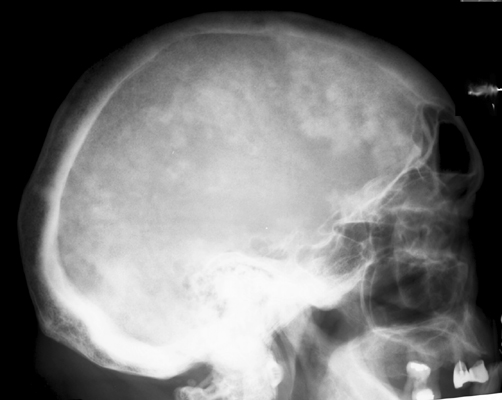

Plain film of the skull reveals a large mottled area of radiolucency with small areas of increased density within it. The MR image of the skull reveals a thickened, enlarged cranium with increase in the marrow space. Two bone scan images also reveal increased activity in the skull, more localized to one side, characteristic to the localized disease seen in Paget's. This is classic cranial involvement of Paget's. In the cranium, bone sclerosis may produce circular radiodense lesions in one area, whereas osteoporosis circumscripta is noted elsewhere. In the skull, the common region of involvement is the cranial vault. The osteolytic phase is called osteoporosis circumscripta and appears as multiple geographic, well-demarcated regions of bone resorption that may be mistaken for metastases. Focal radiodensities occur as pagetoid bone is formed. In the quiescent phase, there is a radiodense cotton-wool appearance with a thickened vault.

Lateral skull - Click on the image for a larger versionAMRI skull - Click on the image for a larger versionBBone scan skull - Click on the image for a larger versionC